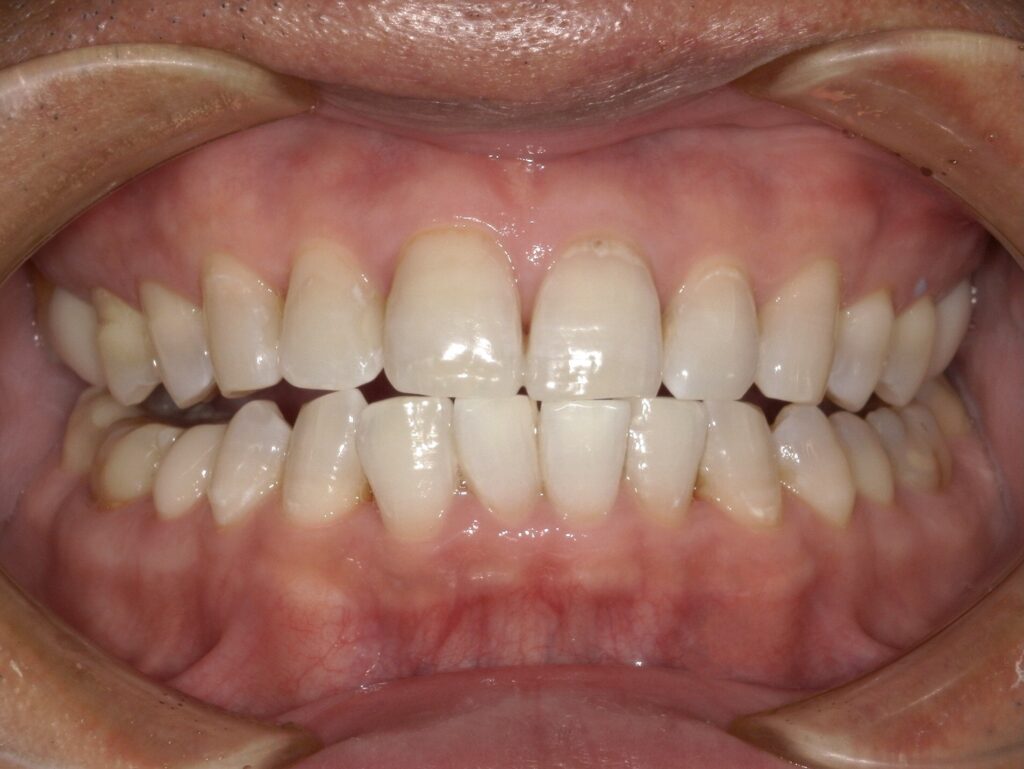

【A様】

Before

After

年齢 | 30代前半 |

性別 | 女性 |

主訴 | 歯を白くしたい |

施術内容 | オフィスホワイトニング3回、ホームホワイトニング |

治療期間 | 半年に一度ほど定期的なオフィスホワイトニングとご自宅でのホームホワイトニングで白さを維持されています。 |